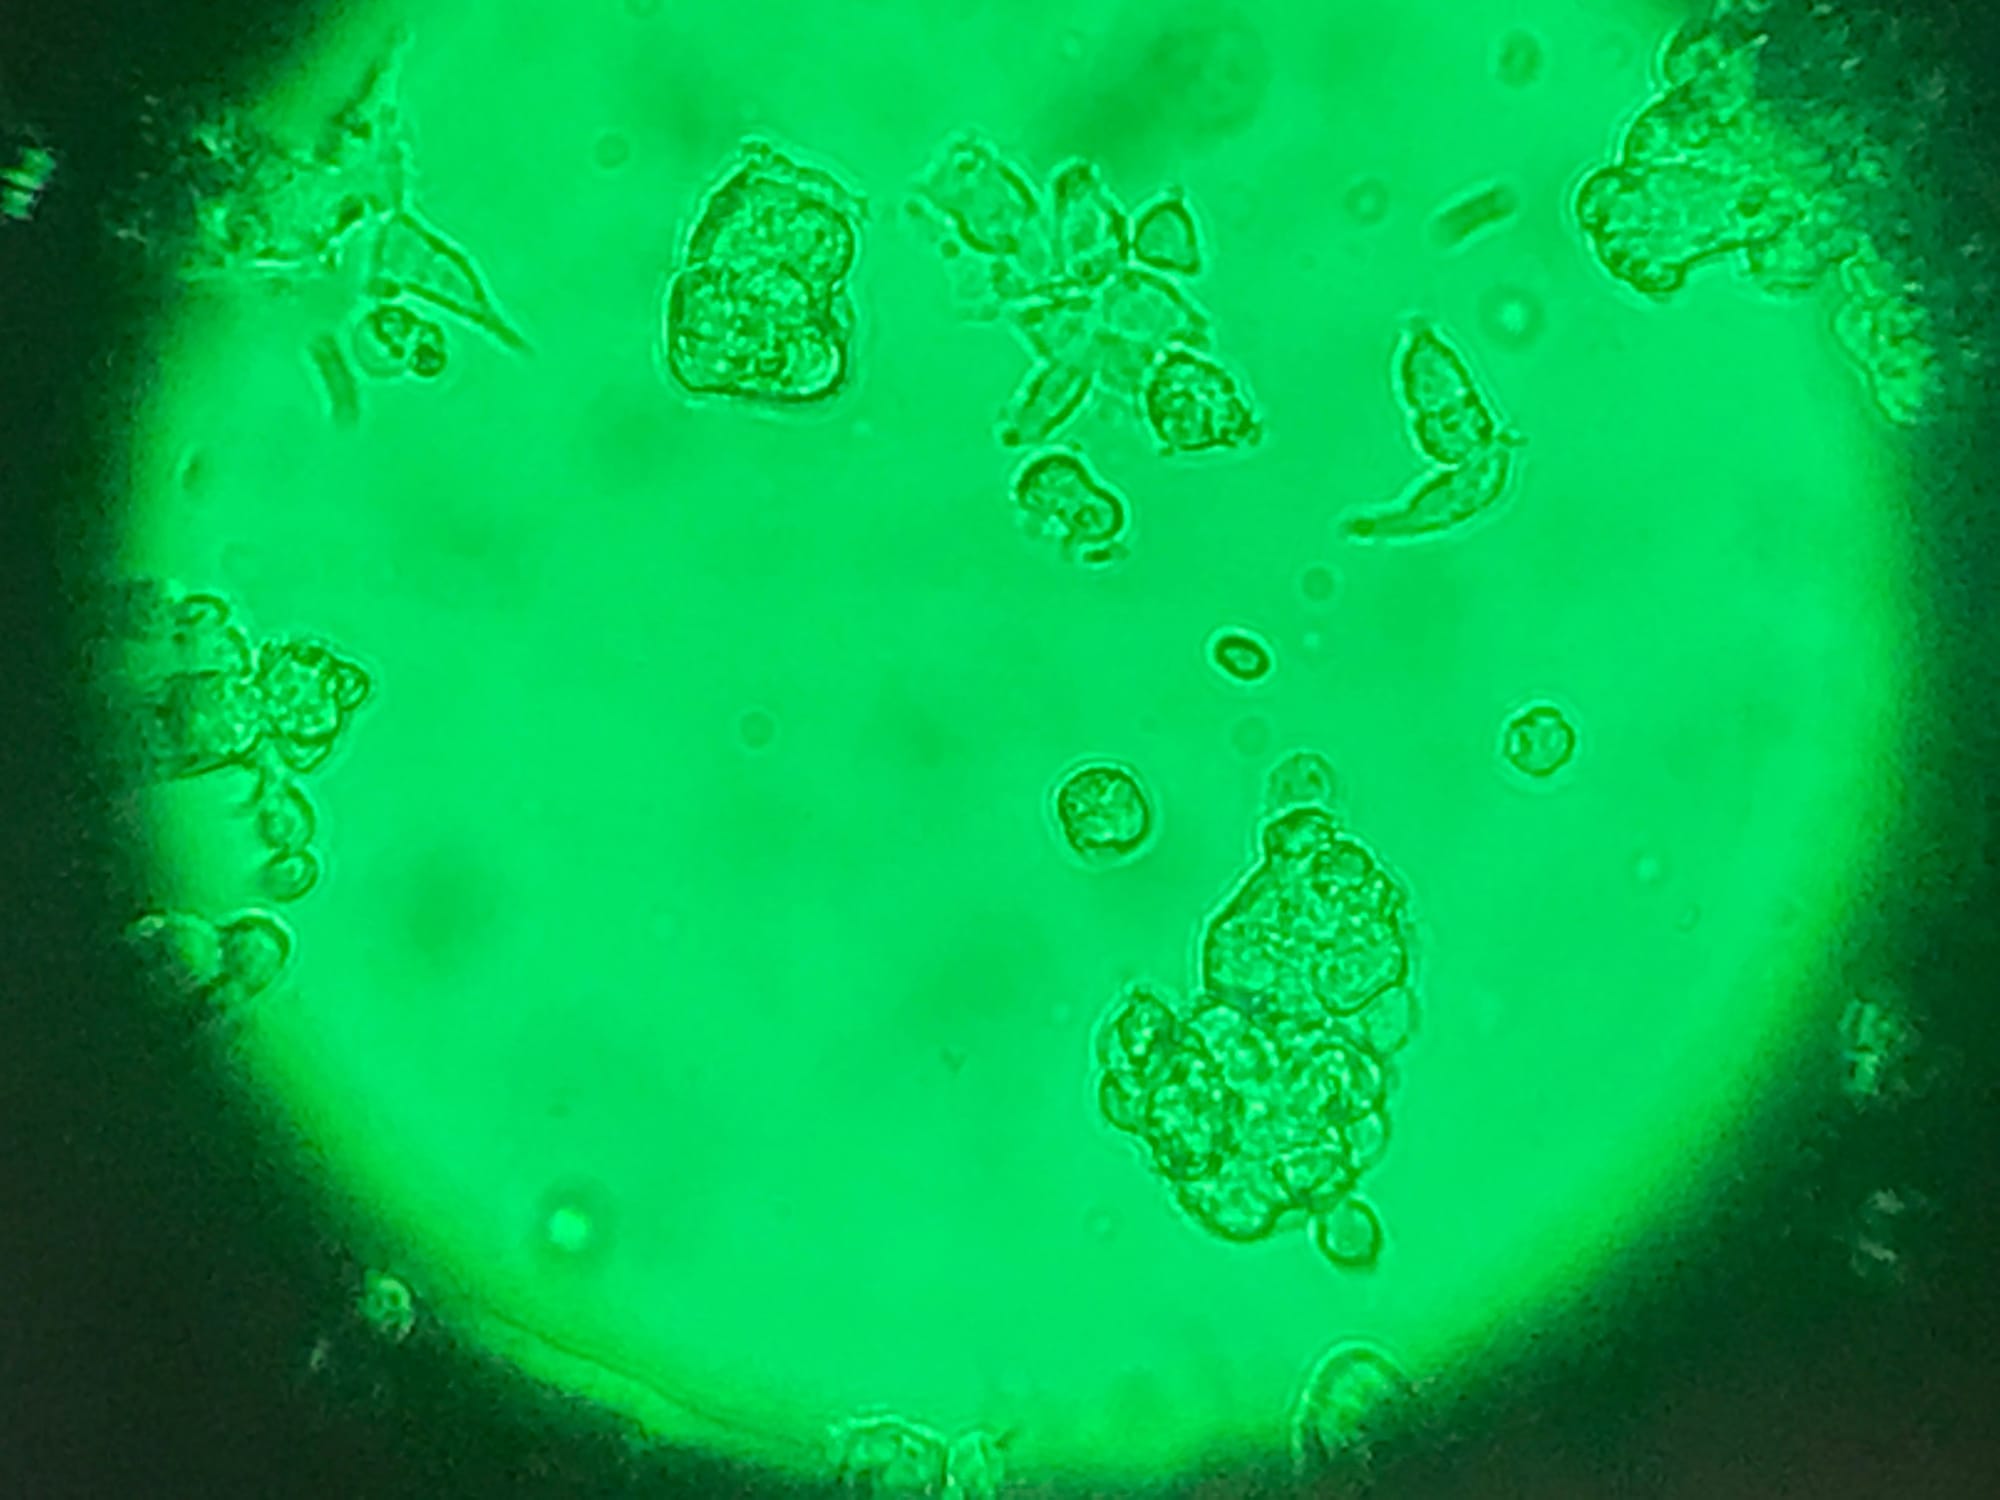

Dr. Wohl brings extensive expertise in preclinical drug development, having established and optimized a range of animal models for malignant glioma studies

His deep commitment to advancing the treatment of primary central nervous system (CNS) tumors is reflected in his parallel engagement in both clinical and translational research.